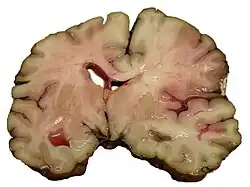

![]() | |

| CT scan of the brain showing a prior right-sided ischemic stroke from blockage of an artery. Changes on a CT may not be visible early on.[1] | |